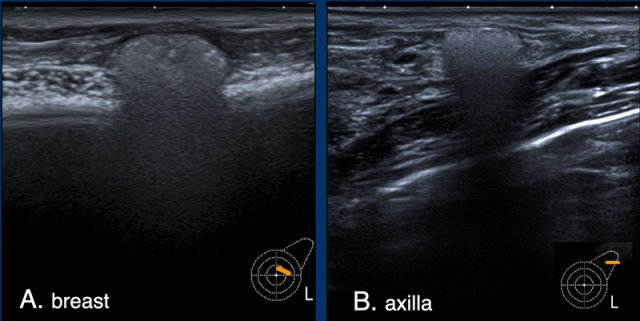

Extracapsular rupture

Extracapsular silicone implant rupture is defined as rupture of both the implant shell and the fibrous capsule with macroscopic silicone leakage that extends beyond the fibrous capsule into the surrounding breast tissue and beyond.

The Silicone which is beyond the capsule causes an acustic shadow called "snowstorm" or "dirty shadow" (figure).

A. There is free Silicone visible outside of the envelope/capsular complex. This is a sign of extracapsular rupture. However there were no other signs of rupture of the prosthesis.

This probably is a Silicone deposit of an older implant that was removed because of extracapsular leakage.

B. The snowstorm sign in an axillary lymph node is highly specific for Silicone deposition in the lymph node.

US is more sensitive than MRI in finding these lymph node deposits.